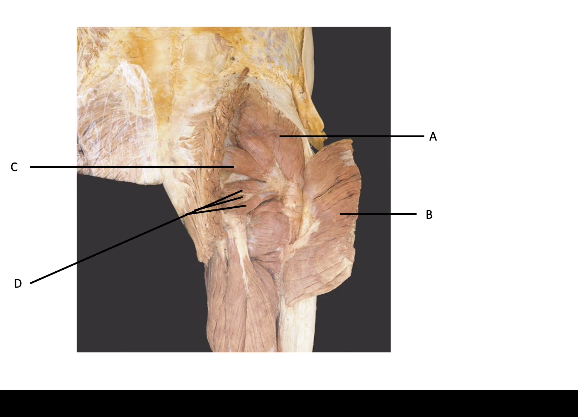

A = gluteus medius B = gluteus maximus C = piriformis D = other lateral rotators